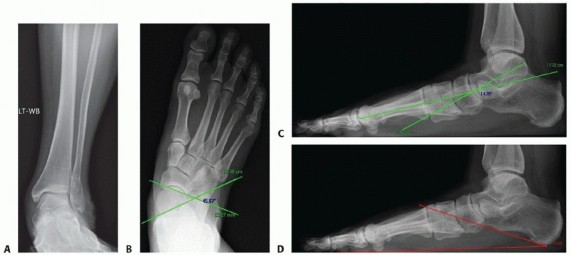

Also, obtain bilateral weight-bearing AP, lateral, and mortise ankle radiographs to evaluate for ankle instability (dorsal talar beaking and distal tibial exostoses), valgus tilt of the talus (deltoid laxity), tibiotalar joint arthritis, and subfibular impingement (FIG 2A).

The talonavicular coverage angle can be measured on the AP foot radiographs. This angle is measured between a line drawn parallel to the articular of the talus and a second line drawn parallel the articular surface of the navicular on the AP radiograph (FIG 2B). This represents the amount of forefoot abduction through the talonavicular joint.

The lateral talo-first metatarsal angle can be measured on lateral foot radiographs and determines the amount of collapse about the medial column through the talonavicular joint. This is measured as the angle between a line drawn down the longitudinal axis of the talus and a line drawn down the longitudinal axis of the first metatarsal (FIG 2C). The normal lateral talo-first metatarsal angle ranges from 4 degrees to −4 degrees.

The calcaneal pitch angle can be measured on lateral foot radiographs. This measurement evaluates the amount of pes cavus or planus. The calcaneal pitch is measured as the angle between a line tangent the inferior aspect of the calcaneus to the inferior aspect of the medial sesamoid and a second line drawn tangent to the inferior aspect of the calcaneus and the most inferior aspect of the anterior calcaneus (FIG 2D). Normal values range from 10 to 30 degrees, with a calcaneal pitch ankle less than 10 degrees representing a flatfoot deformity and more than 30 degrees representing a cavus foot deformity.

FIG 2 • A. AP radiograph of the ankle demonstrating subfibular impingement with an associated lateral malleolus fracture in a patient with posterior tibial tendon deficiency. B. AP radiograph of the foot measuring the talonavicular coverage angle. C. Lateral radiograph of the foot measuring the talo-first metatarsal angle. D. Lateral radiograph of the foot measuring the calcaneal pitch angle.*